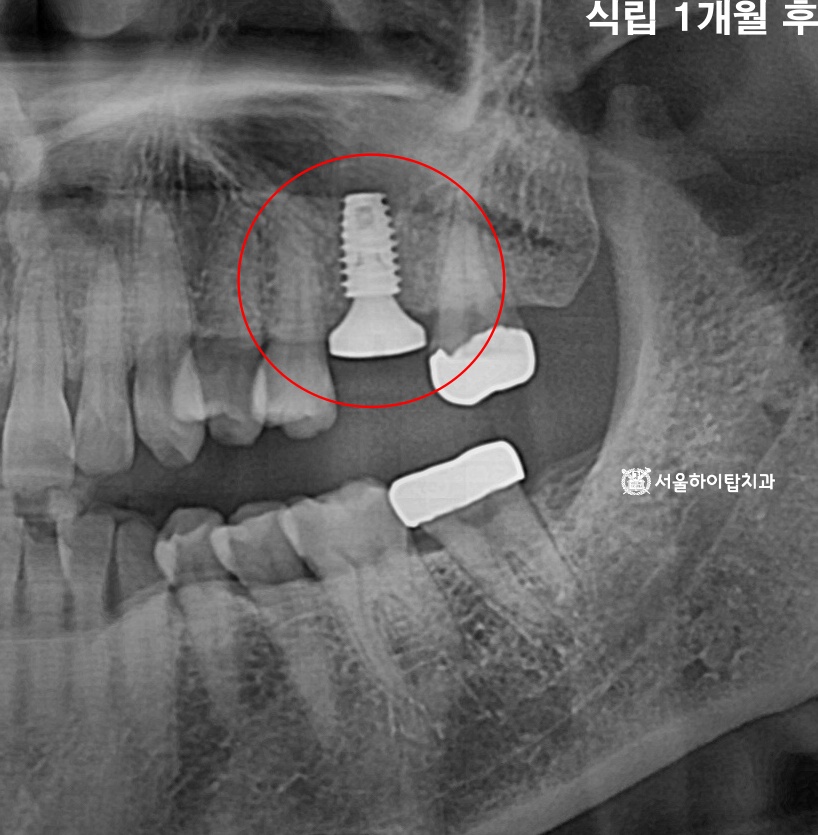

임플란트 식립 완료

만수동 치과 에서는 상기 시뮬레이션을 통해 계획된 위치에

임플란트가 안전하게 식립된 모습을 확인할 수 있습니다.

이후 약 3~4개월간 ‘골유착'(Osseointegration) 과정이 이루어지며,

이 기간 동안 임플란트 픽스처가 주변 치조골과

점차 단단하게 결합하게 됩니다.

특히 식립 4주 전후에는 엑스레이를 통해

픽스처가 위치 변화 없이 안정적으로 유지되고 있는지,

염증 소견은 없는지 등을 다시 한 번 확인하여

예후를 평가하게 됩니다.